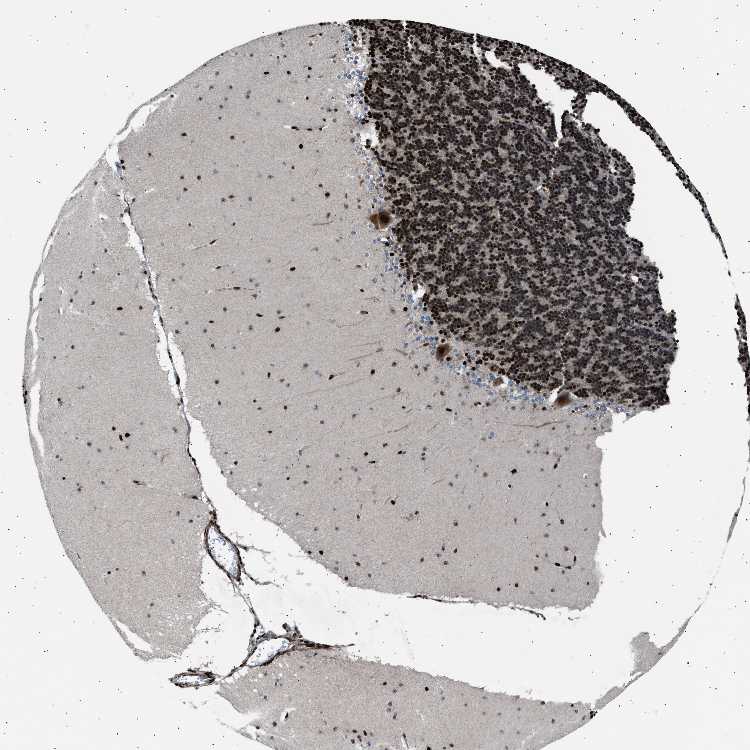

CEREBELLUM - Antibody stainingi

Antibody staining in the annotated cell types in the current human tissue is reported as not detected, low, medium, or high, based on conventional immunohistochemistry profiling in selected tissues. This score is based on the combination of the staining intensity and fraction of stained cells.

Each image is clickable and will lead to virtual microscopy that enables deeper exploration of all samples and also displays staining intensity scores, fraction scores and subcellular localization as well as patient and tissue information for each sample.

Antibody HPA015324

Purkinje cells High

Cells in granular layer High

Cells in molecular layer High